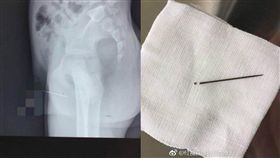

刺痛10多年 他屁股竟扎8根繡花針

身體若是出現不同於以往的異狀,為了謹慎起見,還是前往...

童拿繡花針插下體 取出竟生鏽斷兩半

對自己身體感到好奇也要小心!中國大陸遼寧瀋陽一名12...